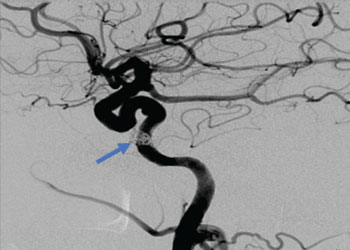

Endovascular:

CME:

Direct Carotid Cavernous Fistula (CCF)

Author: Jonathan L. Brisman M.D., F.A.C.S., Read More!